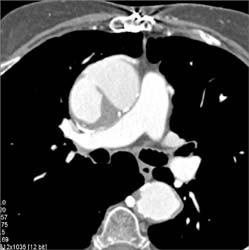

Lung Cancer With Necrotic Nodes